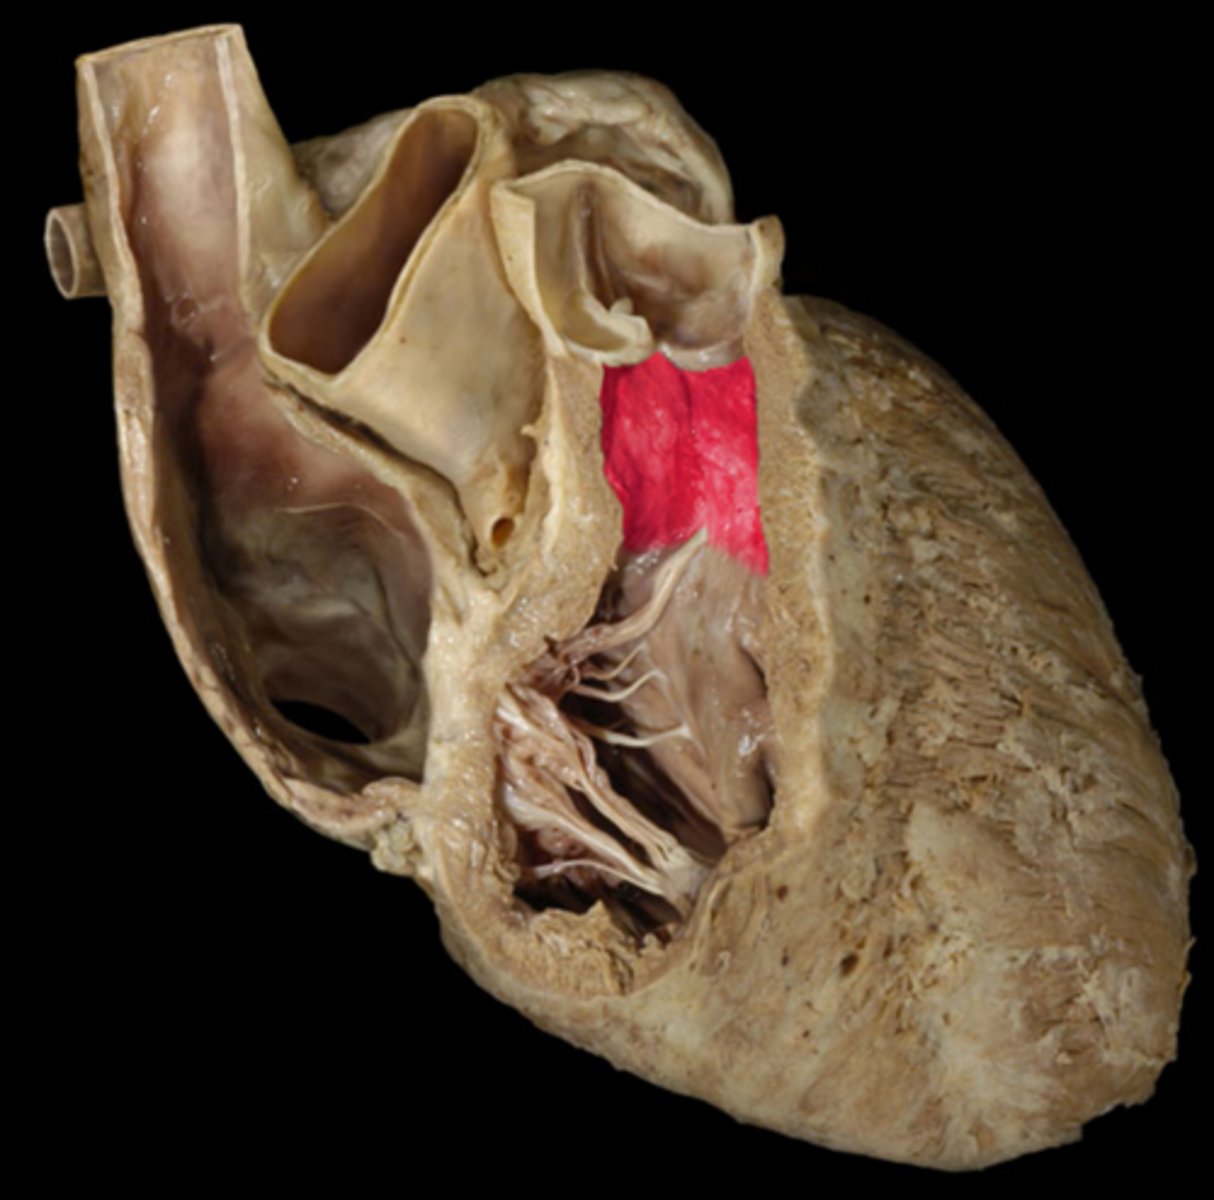

mitral valve

valve between the left atrium and the left ventricle; bicuspid valve

shaped like a bishops hat

aortic vestibule

the narrowing "outflow part" of the ventricle leading to the ascending aorta

opening of ascending aorta

probe going through the aorta

aortic valve

all three cusps make up the...

left atrioventricular orifice

opening between left atrium and left ventricle